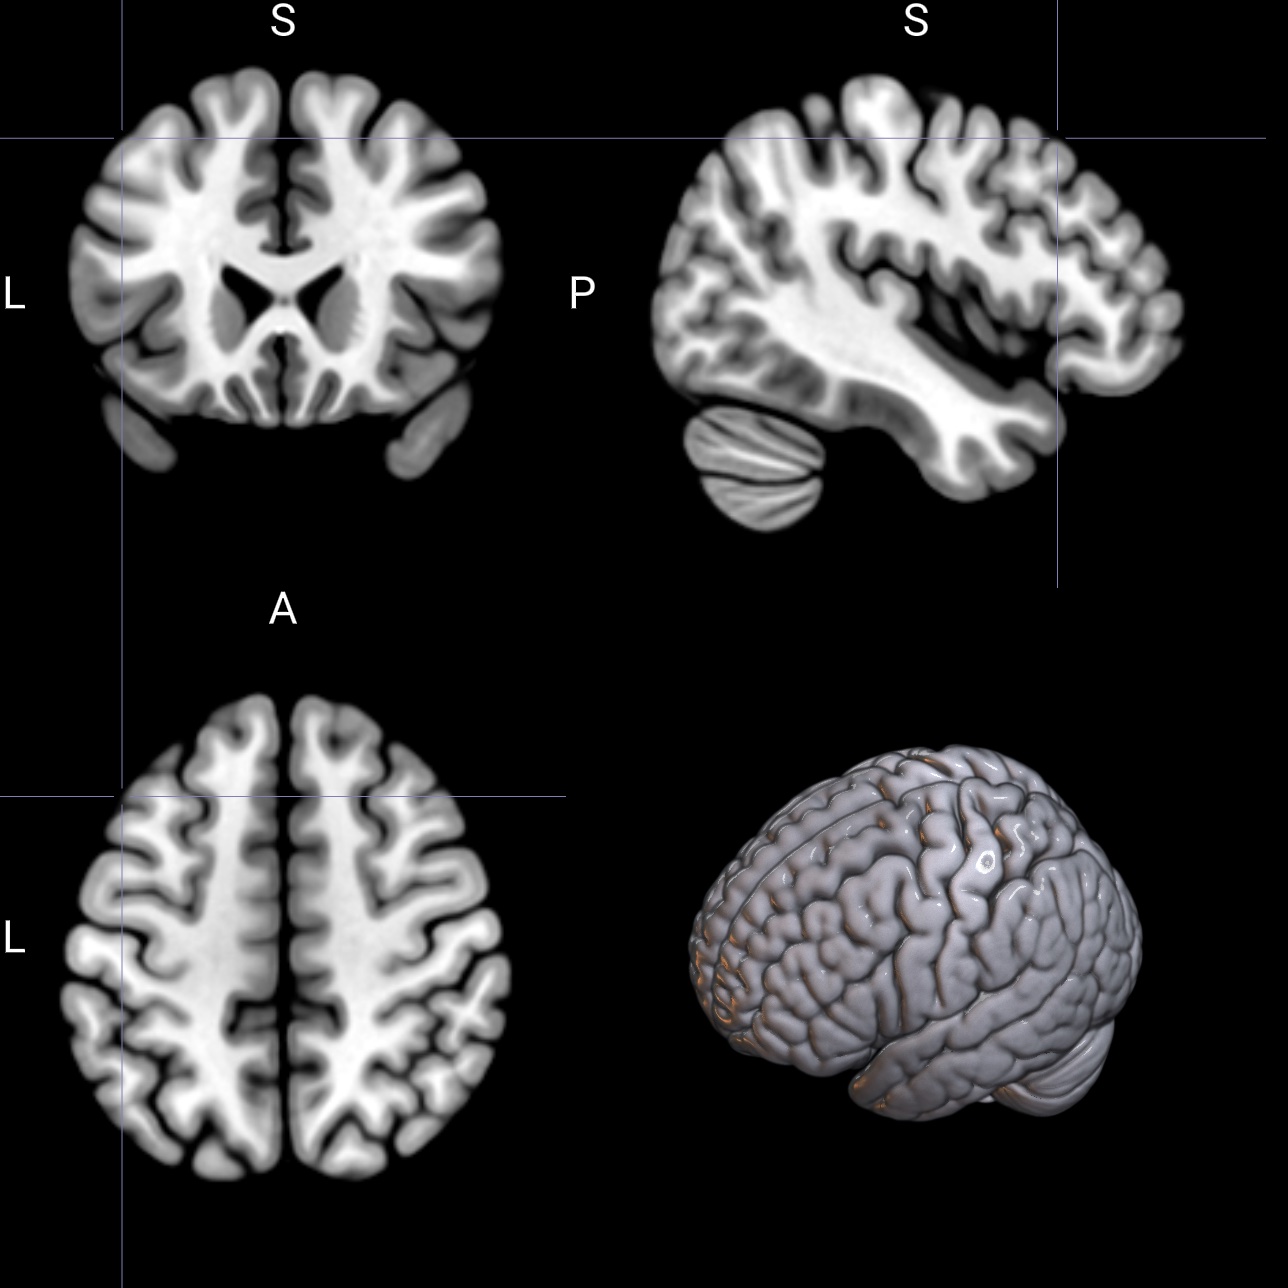

specifically, choose View/Multiplanar(A+C+S+R) to see four views simultaneously: the axial, coronal, sagittal and rendering. Clicking on the rendering will show you the corresponding location on the 2D slices.